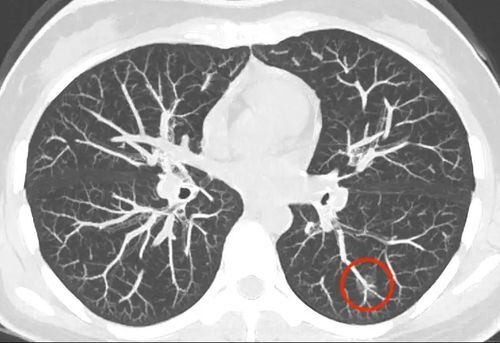

肺部磨玻璃结节,是我们在胸部CT上可以看到的类圆形的模糊影,看起来感觉就像磨砂玻璃一样。

磨玻璃结节,根据密度不同,分为“纯磨”(pure ground-glass nodules,pGGN)和“混磨”(mixed ground-glass nodule,mGGN)。

纯磨玻璃结节是是指CT肺窗上的局灶性磨玻璃样阴影,且结节内不含(能遮挡血管或支气管结构的)实性成分。

胸部CT显示的肺内密度轻度增高云雾状淡薄影,但通过病灶仍能看到肺纹理影,就像透过磨砂玻璃观察一样。可以是弥漫性散在生长,也可以聚集在局部,看起来像一个小磨玻璃结节。